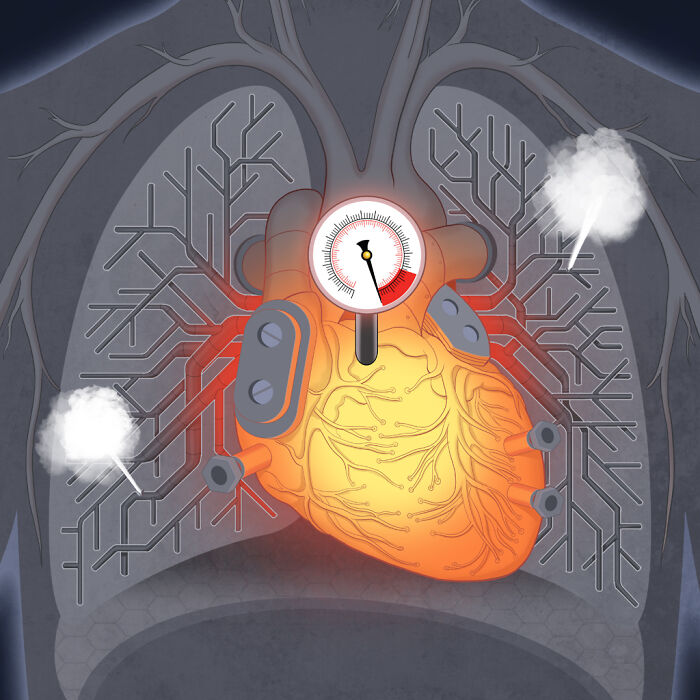

Hypertension